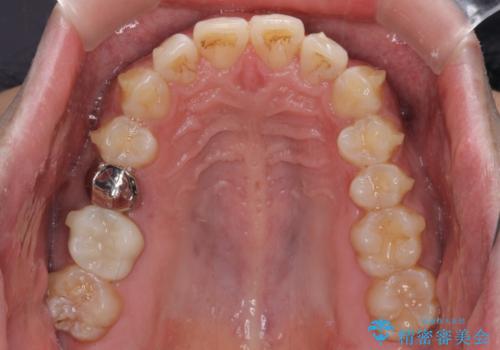

破折して抜歯が必要となった歯の後ろの歯は、根管治療が必要な状態であったので、根管治療を行い、矯正治療後にインプラント部の補綴治療と同時にセラミッククラウンを装着しました。

矯正治療以外に費用負担がかかることになりましたが、気になるところ全てを処置することができ、患者様には大変満足していただきました。